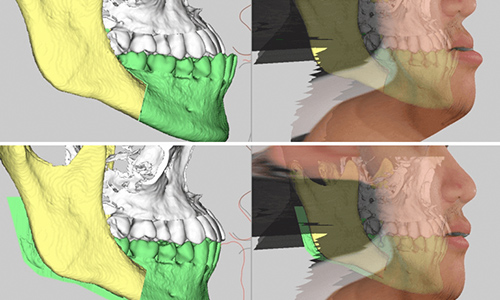

あなたのお口の中の3Dモデルを作成し、それを元に治療計画を立てます。そしてマウスピース型の矯正装置をこのように段階的に設計していきます。

矯正治療をご希望のすべての方には、治療結果の歯列をモニター上で確認できる「outcome simulator(アウトカムシミュレーター)」をお受け頂けるなど、より患者様に分かりやすい治療のご提案をしています。

日本橋はやし矯正歯科では、3Dデジタル矯正システムを応用した

マウスピース矯正での治療が可能となりました。